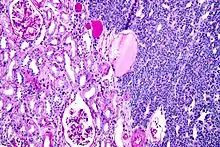

| Micrograph of a metanephric adenoma with structures reminiscent of those seen in papillary renal cell carcinoma. H&E stain. | |

Metanephric adenoma (MA) is a rare, benign tumour of the kidney, that can have a microscopic appearance similar to a nephroblastoma (Wilms tumours),[1] or a papillary renal cell carcinoma.

Histopathology

Metanephric adenoma is diagnosed histologically. The tumours can be located at upper pole, lower pole and mid-hilar region of the kidney; they are well circumscribed but unencapsulated, tan pink, with possible cystic and hemorrhagic foci. They show a uniform architecture of closely packed acinar or tubular structures of mature and bland appearance with scanty interposed stroma.[3][4][5][6][7] Cells are small with dark staining nuclei and inconspicuous nucleoli. Blastema is absent whereas calcospherites may be present. Glomeruloid figures are a striking finding, reminiscent of early fetal metenephric tissue. The lumen of the acini may contain otherwise epithelial infoldings or fibrillary material but it is quite often empty. Mitoses are conspicuously absent.[3][4][5][6][7] In the series reported by Jones et al. tumour cells were reactive for Leu7 in 3 cases of 5, to vimentine in 4 of 6, to cytocheratin in 2 of 6, to epithelial membrane antigen in 1 of 6 cases and muscle specific antigen in 1 of 6.[5] Olgac et al. found that intense and diffuse immunoreactivity for alpha-methylacyl-CoA racemase (AMACR) is useful in differentiating renal cell carcinoma from MA but a panel including AMACR, CK7 and CD57 is better in this differential diagnosis.[8] Differential diagnosis may be quite difficult indeed as exemplified by the three malignancies initially diagnosed as MA that later metastasized, in the report by Pins et al.[9]